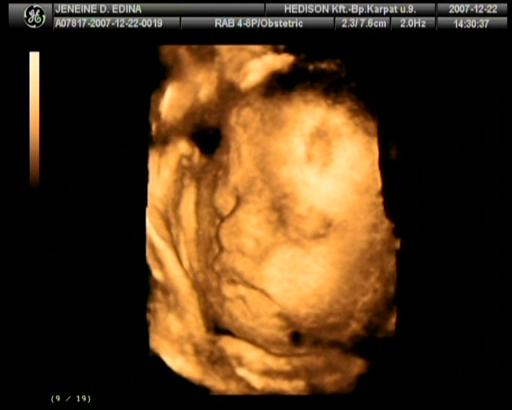

2007.december 25.-re voltunk kiírva. Védőnőm 12. 07.-én pénteken jött hozzánk azzal a céllal, hogy összeírjuk mindazt ami szükséges a nagy napra. Szombaton megvettük a nadrágpelenkát és a popsitörlőt, így már mindent beszereztünk babánknak. Vasárnap még hab mesefigurákat festettünk férjemmel. Nem gondoltuk, hogy valami elkezdődik pocakomban. Este hamar kidöltem,

„szépségápolási” műveletet elvégeztük és elmentem aludni kb. 21:30 -kor. Férjem éjfél körül jött aludni. 12.10.-én 0:30 -kor arra ébredtem, hogy erős vizelési inger kapott el, alig éretm a mosdóba. A nyákdugó távozott magzatvízzel! Halkan szóltam Attinak, hogy kell mennünk. A gyér éjjeli forgalomnak köszönhetően kb.15 perc alatt értünk a Szülészeti Klinikára. Meglepő módon üres volt a parkoló.

Felsétáltunk a szülőszobára és az éjszakás szülésznő felvett az osztályra.

Egy ujjnyira voltam kinyílva. Sétáltam a folyosón, apával csináltunk utolsó pocakos képet Lara a pocakban címszóval, megszakításokkal CTG-n figyeltük Larát és a fájások jelentkezését12:15-ig. Közben reggel Felhívtam fodrászomat, hogy lemondjam a mai időpontot (fodrászom jó szülést kívánt), aztán orvosomat (aki szabadságon volt) 08:00-körül és mondtam, hogy mi a helyzet. Ő bátorított és mondta számíthatok rá, itt van. Délután bejön, addig is délig ihatok folyadékot, aztán bekötik az infúziót. Anyukámat is hívtam, hogy mi lesz a mai programom. Mondta, hogy legyek bátor, picit fájni fog, DE megéri és csak a jóra fogok emlékezni. Mondtam neki, hogy nyugodt vagyok az orvosom is bejön hozzánk a szabadságról.